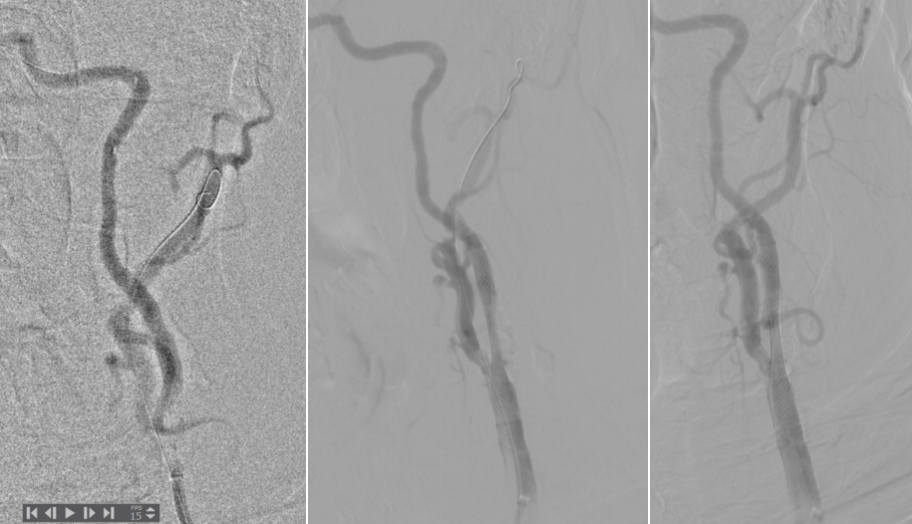

术前头颈CTA提示左侧颈总动脉(L-CCA)的狭窄处钙化严重,且L-CCA和主动脉弓的夹角很锐(图1),显然,这样的颈动脉狭窄更适合剥脱(CEA)。但由于患者高龄,且20天前经历过心梗,存在全麻手术禁忌,因而安排了CAS。

图1. 术前CTA。